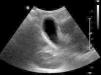

Presentamos el caso de un niño de 3 años que consulta por dolor en hemiabdomen derecho de 72 h de evolución, asociando vómitos, febrícula y deposiciones hipocólicas. En la exploración física destaca dolor a la palpación en la región supraumbilical y el hipocondrio derecho, con signo de Blumberg positivo. En la analítica presenta leucocitosis con desviación izquierda (27.000 leucocitos [neutrófilos 77%, cayados 4%]), alteración en la coagulación (TP 61%, fibrinógeno: 777mg/dl) y elevación de reactantes de fase aguda (PCR de 112,5mg/l). Se solicita una ecografía abdominal urgente (fig. 1), donde se sospecha CAA.

Se ingresa para analgesia, manteniéndose en dieta absoluta e iniciando tratamiento antibiótico por vía intravenosa con gentamicina, amoxicilina-ácido clavulánico y metronidazol. A las 12 h del ingreso, persiste dolor a la palpación abdominal, aunque de menor intensidad, sin vómitos ni alteraciones deposicionales. Se realiza control analítico, objetivándose aumento de la PCR a 218mg/l, y control ecográfico, donde persisten signos inflamatorios en el área vesicular, y grasa adyacente, mínima cantidad de líquido de aspecto inflamatorio y mínimo plastrón en asas próximas. Se solicita una tomografía computarizada abdominal urgente (fig. 2), en la que se reafirma el diagnóstico de CAA.